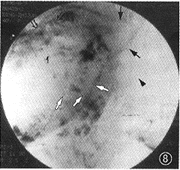

图9 例4。L-TAE术后3个月取代性肝右动脉DSA复查见碘油沉积和缩小的瘤体上下边缘部又有对比剂充盈,少数肝静脉支早显(↑),提示AHVS未完全闭塞

3.本组病例并发的AVS L-TAE术后摄片所见:并发AVS的22例CHL中,21例在L-TAE术后即时行X线摄片发现:碘油混合剂通过未完全闭塞的AVS再充盈于少部分门静脉周围支或引流静脉者11例(图2,4);DSA显现的AVS完全闭塞而未见任何静脉充盈碘油混合剂者10例(图6),但其中1例(AHVS)于L-TAE术后3个月DSA复查又见少部分肝静脉支早显(图9);所有21例CHL的血管湖内皆见到碘油混合剂的较完全或完全沉积(图2,4,6)。